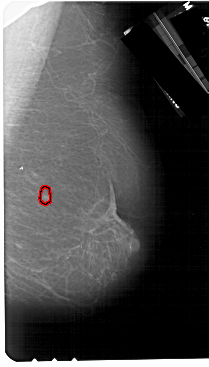

A_1267_1.LEFT_MLO

LEFT_MLO LINES 5491 PIXELS_PER_LINE 3691 BITS_PER_PIXEL 12 RESOLUTION 43.5 NON_OVERLAY

FILE: A_1267_1.RIGHT_MLO.OVERLAY

TOTAL_ABNORMALITIES 1

ABNORMALITY 1

LESION_TYPE MASS SHAPE OVAL MARGINS CIRCUMSCRIBED

ASSESSMENT 4

SUBTLETY 4

PATHOLOGY BENIGN

TOTAL_OUTLINES 1

BOUNDARY